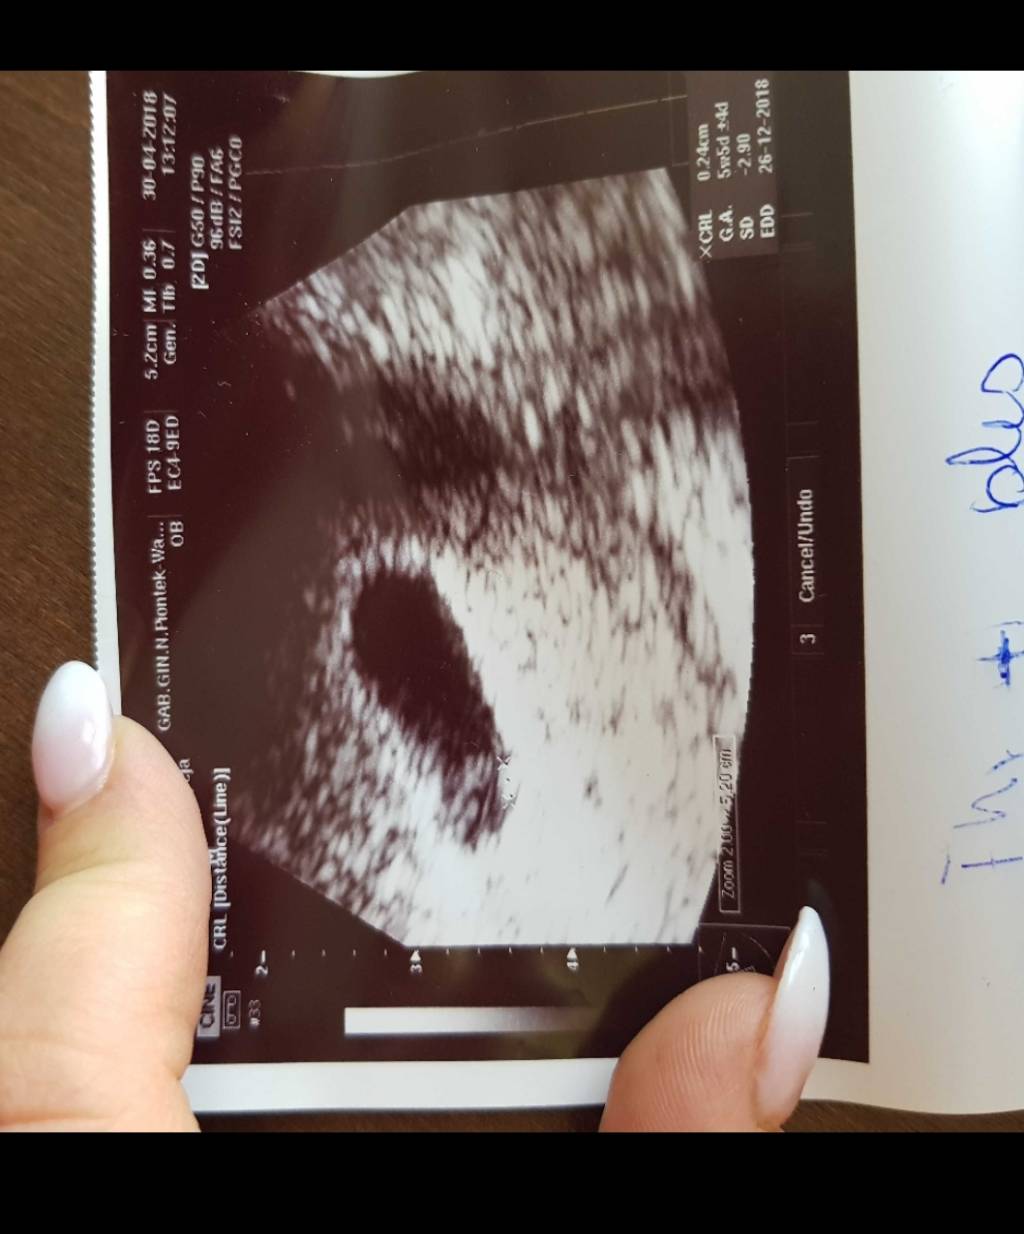

Hej dziewczyny!!! U mnie duzo sie dzialo slub, pogrzeb... nie dam rady was nadrobic. 24.04 hcg 5660 . Bylam dzis u lekarza dostałam termin na 26.12 i widzialam pulsujace serduszko [emoji7][emoji7][emoji7]

Hej dziewczyny!!! U mnie duzo sie dzialo slub, pogrzeb... nie dam rady was nadrobic. 24.04 hcg 5660 . Bylam dzis u lekarza dostałam termin na 26.12 i widzialam pulsujace serduszko [emoji7][emoji7][emoji7]Zobacz załącznik 852085